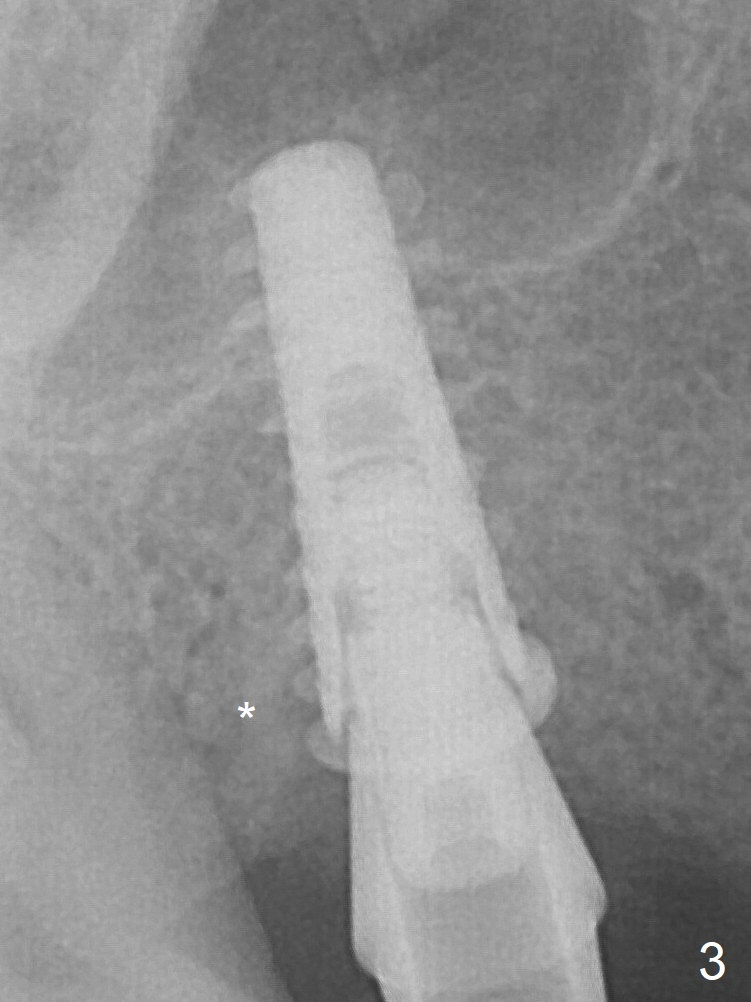

Following the last drill (3.8 mm) for 11 mm, a 4.5x11 mm dummy implant is placed 2 mm subgingival (Fig.2; *: space of the palatal socket). In fact the sinus lift is done by the implant, since the bone plug after Magic Drill is present in the apical portion of the osteotomy when the last drill is finished prior to implant placement. After the dummy implant is removed, the definitive one (the same size) is placed with >50 Ncm, followed by placement of a 4.5x4(3) mm abutment and VeraGraft mixed with autogenous one (Fig.3 *). VeraGraft granules are finer than Vanilla one (.25-1 mm vs. .5-1 mm).